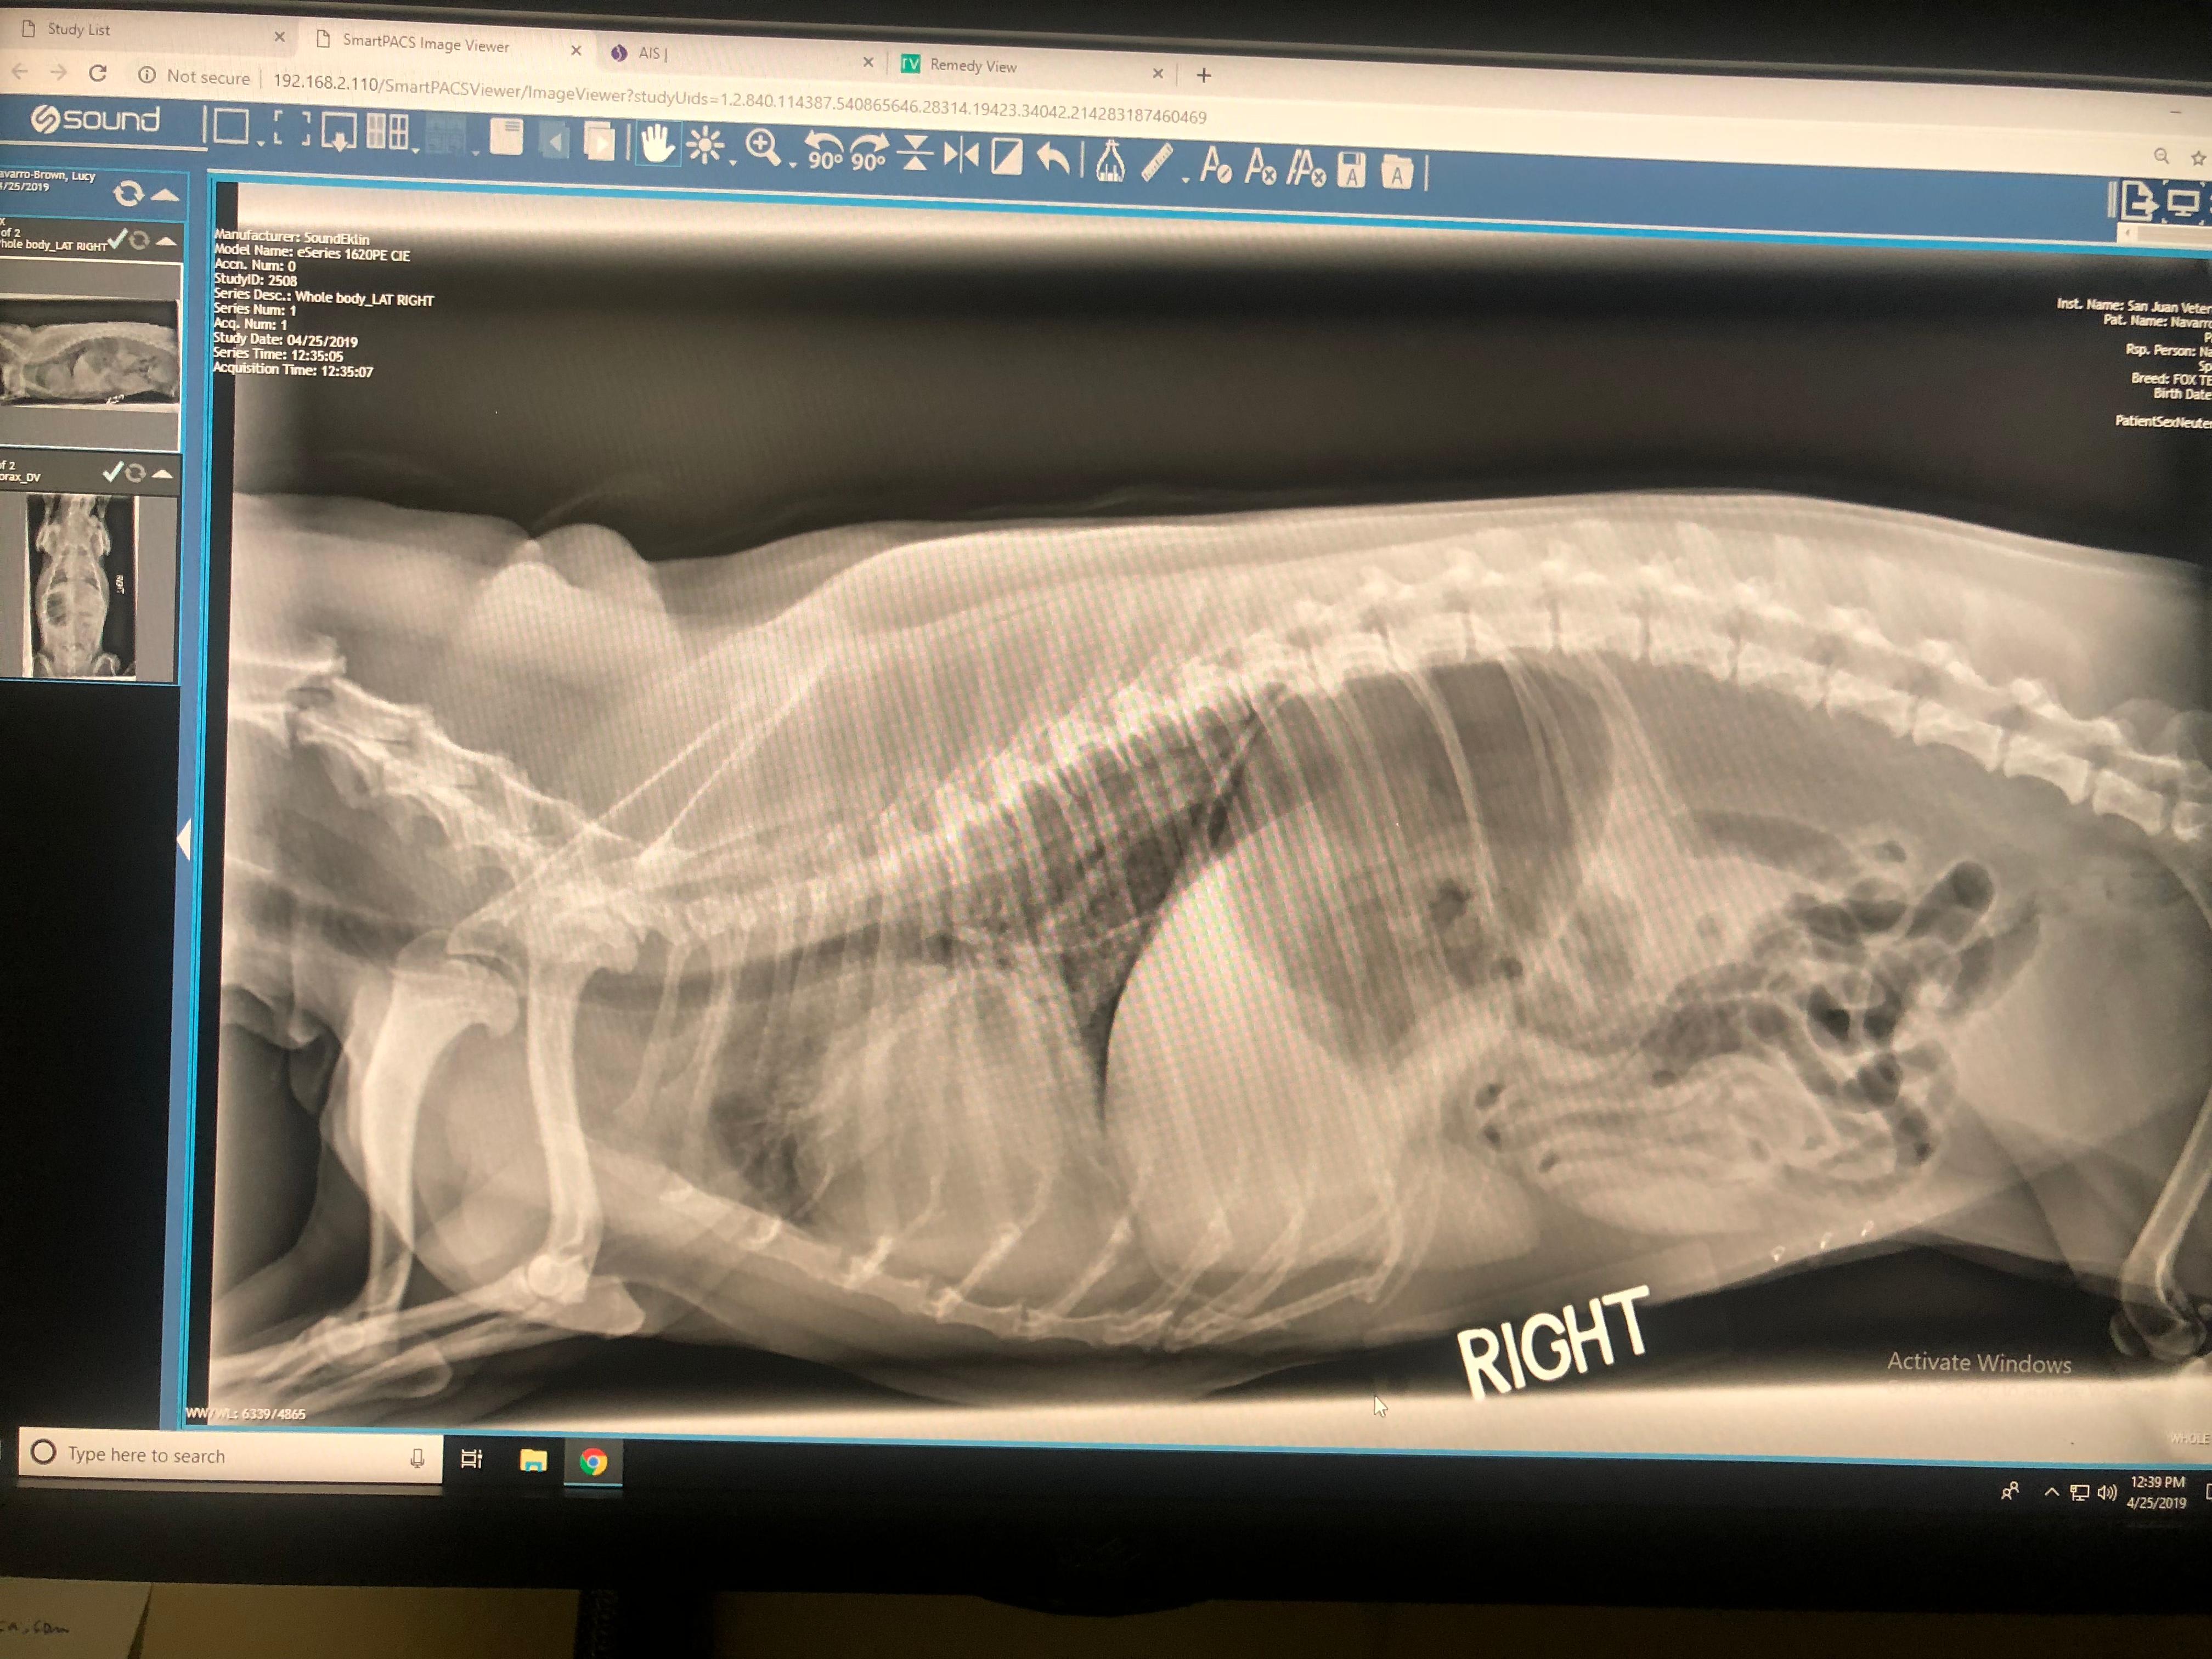

My dog recently died, the vet still doesn’t know the cause. While we’re grieving we borrowed our other dog from my step family, she’s come home with us but now she vomited, just like my other dog did when she first got sick. Daisy, my step family’s dog, ate grass from outside and just coughed foam into her water. I’ve attached the X-ray from Lucy, my dog who has just passed, during her final times. Can you tell me if Daisy could get this too, or what she has? I really can’t handle losing her too

Hi, from the x-rays Lucy seemed to have an enlarged heart wether it was just a cardiomyopathy or possibly a mass in her right chest it is impossible to tell. From these xrays I can tell you that Lucy s condition was not contagious, but most likely cardio-respiratory in its origin. I would have Diasy’s Chest checked over but I would try not to worry too much, sending you positive thoughts.